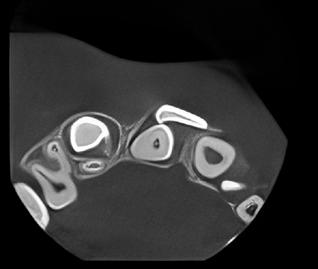

delta@delta-rengoering dk

deltaa@ddeltaa--rengoering d dk

www.delta-rengoering.dk

Hvis jobannoncen bliver indrykket på både Dentaljob.dk og i Tandlægebladet, får du 50 % rabat på annoncen i bladet

BAGGRUND – Centralt kæmpecellegranulom (Central giant cell granuloma – CGCG) er en sjælden, godartet læsion, som nærmest udelukkende er lokaliseret til kæberne. Det har kliniske, radiologiske eller histologiske ligheder med flere andre intraossøse læsioner. Ætiologien er stadig ukendt, men det viser sig, at genetiske mutationer er associeret med forekomsten af CGCG.

PATIENTTILFÆLDE – Tre drenge i alderen fem og seks år blev alle diagnosticeret med og behandlet for større CGCG-læsioner med få måneders mellemrum på Tand-, Mund- og Kæbekirurgisk Klinik, Aarhus Universitetshospital.

KONKLUSION – Det er yderst relevant at følge børn med spontant og tidligt tandtab i kommunal tandpleje. Ved mistanke om patologiske forandringer henvises til hurtig udredning og diagnostik i hospitalsregi for at klarlægge diagnose og minimere skader på blivende tandanlæg og omkringliggende strukturer.

EMNEORD Central giant cell granuloma | giant cell lesions | jaw neoplasm | benign bone diseases

CHRISTIAN LIND AXELGAARD, specialtandlæge i tand-, mund- og kæbekirurgi, Speciialklinik for kæbekirurgi, Silkeborg

KIMIE BOLS ØSTERGAARD, tandlæge i videreuddannelse til specialtandlæge i tand-, mund- og kæbekirurgi. Kæbekirurgisk Afdeling, Aalborg Universitetshospital

SVEN ERIK NØRHOLT, klinisk professor, specialtandlæge i tand-, mund- og kæbekirurgi, ph.d., overtandlæge, Afdeling for Tand-, Mund- og Kæbekirurgi, Aarhus Universitetshospital, og Sektion for Kæbekirurgi og Oral Medicin, Institut for Odontologi og Oral Sundhed, Aarhus Universitet

PER JOHAN SIXTEN BLOMLÖF, overtandlæge, docent, ph.d., specialtandlæge i tand-, mund- og kæbekirurgi, Afdeling for Tand-, Mund- og Kæbekirurgi, Aarhus Universitetshospital

STEEN BÆRENTZEN, overlæge, Patologiafdelingen, Aarhus Universitetshospital

OTTO THORSSON, specialtandlæge i tand-, mund- og kæbekirurgi, Afdeling for Tand-, Mund- og Kæbekirurgi, Aarhus Universitetshospital Accepteret til publikation den 13. maj 2025 Tandlægebladet 2025;129:928-34

CKorrespondanceansvarlig førsteforfatter: CHRISTIAN LIND AXELGAARD christianlindaxelgaard@gmail.com

ENTRALT KÆMPECELLEGRANULOM (CGCG) er en sjældent forekommende, benign, destruktiv læsion i kæberne, som af WHO karakteriseres ved en uindkapslet spredning af mononukleære spindelformede og polygonale celler med tilstedeværelsen af osteoklastlignende, multinukleære kæmpeceller i en vaskulær baggrund (1). CGCG udgør ca. 7 % af alle benigne, tumorøse læsioner i kæberne (2). CGCG ses med øget hyppighed ved patienter med RASopatier, som er fænotypisk homogene grupper af genetiske syndromer, forårsaget af patogenetiske stamcellevariationer i dele af RAS/mitogen-activated protein kinase (RAS/MAPK) pathway (Faktaboks) (3); heriblandt neurofibromatose type 1 (NF1) og Noonans syndrom (NS) (4). CGCG forekommer også sporadisk uden kendte stamcellemutationer. Ved patienter med sporadiske CGCG ses også ofte genmutationer i MAPK-pathway proteiner som KRAS, FGFR1 eller TRPV4, hvilket tyder på en genetisk årsag for udvikling af CGCG (5-8).

MAPK-pathway’en er en af de vigtigste og mest undersøgte signaleringspathways. Den er centrum i et molekylært signaleringsnetværk, der styrer vækst, proliferation, differentiering og apoptose. Meget forenklet signalerer den gennem tyrosinkinasereceptorer, der fosforylerer et målprotein som respons på en stimulus, og dette sætter gang i reaktioner, som afgrænses ved defosforylering af et protein downstream. Den fungerer således som en kontakt, der kan tænde og slukke. Hvis der er mutationer i et af proteinerne i denne pathway, kan denne sidde fast i tændt eller slukket tilstand (9).

Sporadiske tilfælde af CGCG forekommer oftest i den anteriore del af mandiblen og debuterer typisk i de første tre årtier af livet (5). I de syndromiske tilfælde ses mere end 90 % posteriort for hjørnetænderne (10).

Læsionerne vokser normalt langsomt, men aggressiv adfærd er ikke ualmindeligt (2). CGCG opdeles i nonaggressive og aggressive subtyper (11), hvilket er vigtigt for valget af behandling, da de aggressive subtyper har en højere recidivtendens (10,12). Histologisk er CGCG identisk med ”Brown tumor”, som ses ved hyperparatyroidisme, men denne tilstand rammer typisk patienter over 50 år. Derfor er det vigtigt med en

Fig. 1. Centralt kæmpecellegranulom i kæbe (A) med ossøs kæmpecelletumor/ osteoklastom i os sacrum til sammenligning (B). Kæmpeceller af osteoklastlignende type (tykke pile) ses af lille til moderat størrelse i kæmpecellegranulomet og af moderat til stor størrelse i kæmpecelletumorer. De mononukleære celler (tynde pile) ses tenformede i fibrøs matrix i kæmpecellegranulomet og anderledes plumpe uden matrixdannelse i kæmpecelletumoren.

Fig. 1. Central giant cell granuloma in the jaw (A) with giant cell tumor of bone/ osteoclastoma in the sacrum for comparison (B). Giant cells of osteoclast-like type (thick arrows) are seen in small to moderate size in the giant cell granuloma and in moderate to large size in the giant cell tumor. The mononuclear cells (thin arrows) appear spindle-shaped in a fibrous matrix in the giant cell granuloma and rather plump without matrix formation in the giant cell tumor.

endokrinologisk udredning for at sikre korrekt diagnose (13). Yderligere er det væsentligt at pointere, at CGCG ikke er det samme som den ossøse kæmpecelletumor/osteoklastom (Fig 1.), der praktisk taget aldrig ses i kæberne, men i stedet i lange rørknoglers epifyser og aksiale skelet og har en helt anden genetisk baggrund med mutation i H3F3A-genet, er endnu mere lokalt aggressiv og endda har en ganske lille risiko for hæmatogen metastasering og malign omdannelse (14).

PATIENTTILFÆLDE 1

Anamnese

En seksårig dreng blev henvist til en second opinion fra Pædiatrisk Afdeling, Aalborg Universitetshospital, hvortil patienten i første omgang var henvist med mistanke om malignitet eller kæmpecelletumor. Patienten havde spontant tandtab i fireårsalderen uden andre symptomer.

Klinik

Ved klinisk undersøgelse blev der observeret en blålig hævelse anteriort i underkæbefrontregionen.

Røntgen

CT-scanning viste diffus osteolyse i mandiblen fra midtlinjen og mod venstre, med involvering af -1,2. Destruktionen og ekspansionen havde ikke forårsaget resorption af tænderne (Fig. 2-3).

Histologi

Tidligere biopsi havde vist CGCG eller perifert kæmpecellegranulom. Ved ny patologisk gennemgang af præparatet blev CGCG bekræftet. Molekylærpatologisk analyse viste en KRASmutation, der understøttede diagnosen.

Patienttilfælde 1 – Præoperativ CT-scanning

Forløb